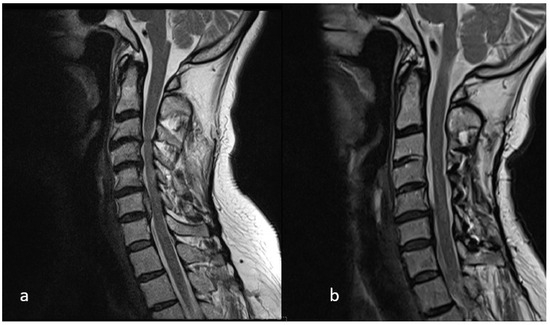

Post-MVC Cervical Kyphosis Deformity Reduction Using Chiropractic BioPhysics Protocols: 1-Year Follow-Up Case Report

Background/Objectives: This case represents the successful treatment of cervical spine injury from high-speed rear-impact motor vehicle collision and abnormal cervical kyphosis with left arm radiculopathy, utilizing conservative spine care rehabilitation methods. This patient was treated with a multimodal treatment approach integrating a cervical [...] Read more.

Background/Objectives: This case represents the successful treatment of cervical spine injury from high-speed rear-impact motor vehicle collision and abnormal cervical kyphosis with left arm radiculopathy, utilizing conservative spine care rehabilitation methods. This patient was treated with a multimodal treatment approach integrating a cervical spine extension traction protocol. Subject and Methods: A 50-year-old male with a history of motor vehicle collision presented with left arm radiculopathy, as well as cervical and upper thoracic spine pain. Notably the cervical spine presented with kyphotic deformity. The patient presented, after a being struck during a rear-end motor vehicle collision, with neck, upper back, and left arm radiculopathy. Prescription medication and traditional chiropractic care proved ineffective for substantive symptom and quality-of-life improvement. Treatment frequency was three times per week for eight weeks using the Chiropractic Biophysics® protocol of mirror image (MI®) postural exercise, spinal adjustment, and cervical spinal traction. On completion of in-office care, the patient was treated monthly, performed home care at least three times per week, and was re-examined at one year. Results: Final examination after eight weeks of care showed significant improvement in cervical lordosis (21.8 degrees), resulting in reduced cervical kyphosis. The patient completed outcome indices before, during, and 12 months after cessation of active care, all indicating improvement. Conclusions: This case report demonstrates both subjective and objective improvement in cervical spine kyphosis and attendant symptoms. The successful treatment of chronic pain, peripheral weakness, and radiculopathy with long-term follow-up using CBP care is documented as well. The treatment was designed to improve sagittal balance and reduce radiographic abnormalities evincing spinal misalignment. Administration of subjective, objective, and health-related quality-of-life outcome indices during, following, and 12 months post-treatment are suggestive of long-term efficacy of Chiropractic BioPhysics® (CBP) treatment methods. Larger studies are needed to substantiate this given the limitations of a case report. Full article